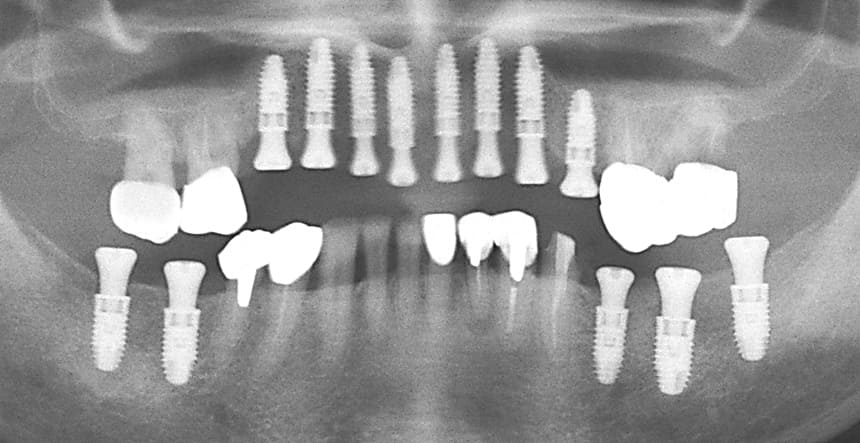

上顎前歯部と両側小臼歯部はインプラント補綴を行い、両側の大臼歯部についても根管治療からやり直して咬合平面を改善すべく補綴を行った。下顎の両側臼歯部に関してもインプラント補綴を行い小臼歯部では根管治療からクラウンによる補綴を行った。左上7番に関しては当初インプラント補綴を行う予定であったがサイナスリフトを伴う治療になることと第一大臼歯までで十分噛めることから埋入せずに経過を見ている。

治療後の口腔内所見である噛み合わせも問題なく機能している。また、一本ずつのインプラント補綴を行ったことでフロスによるケアができ良好な口腔内環境を維持できている。